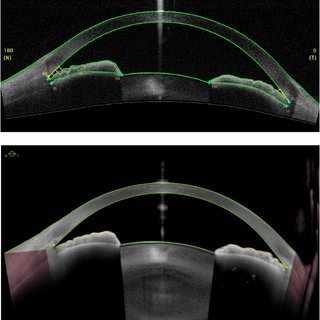

OCT 안구 광학 단층촬영은 망막뿐아니라 전안부 촬영에도 사용되게되는데,

이를 Anterior segment OCT (AS-OCT), 전안부 OCT 라고 합니다.

최근나오는 AS-OCT는 각막의 영상뿐아니라 수정체 후면까지 찍을수 있는 해상도를 지닙니다.

이는 앉은 상태에서촬영하고,

눈에 직접 접촉하지 않고 측정가능하며,

UBM 보다 더 선명한 이미지를 보여줍니다.

다만 홍채뒷부분은 홍채에 가려서 측정이 불가능한 것이 단점입니다.